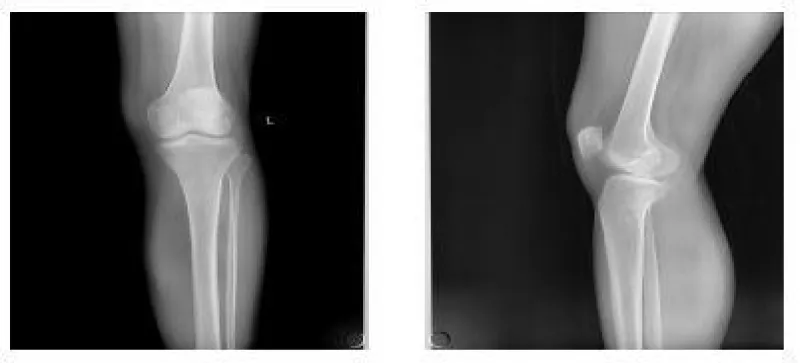

A 56-year-old woman was sent to the emergency department by her family. She sprained her left ankle when she went down the stairs. She had difficulty walking because of a painful left ankle. Specialized physical examination found tenderness in the anterolateral distal tibia and fibular neck. X-ray showed fractures in the tibia lateral border and fibular neck, with no evidence of inferior tibiofibular joint dislocation (Figures 1,2). A computed tomography scan confirmed the presence of Tillaux-Chaput and Volkmann fractures (Figures 3-5).

The anesthetic for the operation was lumbar anesthesia. A posterolateral approach was used to expose the Volkmann fracture. An anterior tibial approach was used to expose the Tillaux-Chaput fracture. The inferior tibiofibular joint was checked carefully. Fractures were reduced and then fixed. Volkmann fracture was fixed by buttress plate, and Tillaux-Chaput fracture was performed by hollow screw. Hook test intraoperative was negative. Anatomical reduction and perfect stability were confirmed by X and CT postoperatively (Figures 6.7). CT scan in the transverse section confirmed that the anterior and posterior edge of the distal fibula is in an arc with the fractures of the tibia. It meant there was no dislocation of the distal fibula. The anterior and posterior ligaments of the inferior tibiofibular ligament are in good condition.